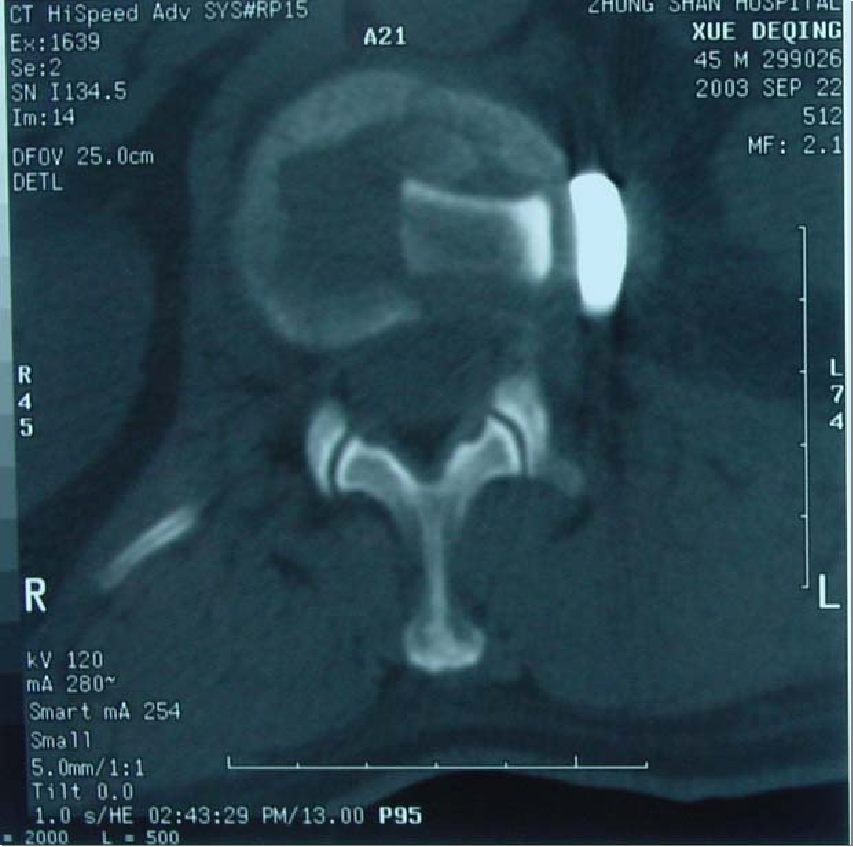

侧前方减压术后CT表现

术后CT表现

术前CT可见骨折块明显压迫脊髓